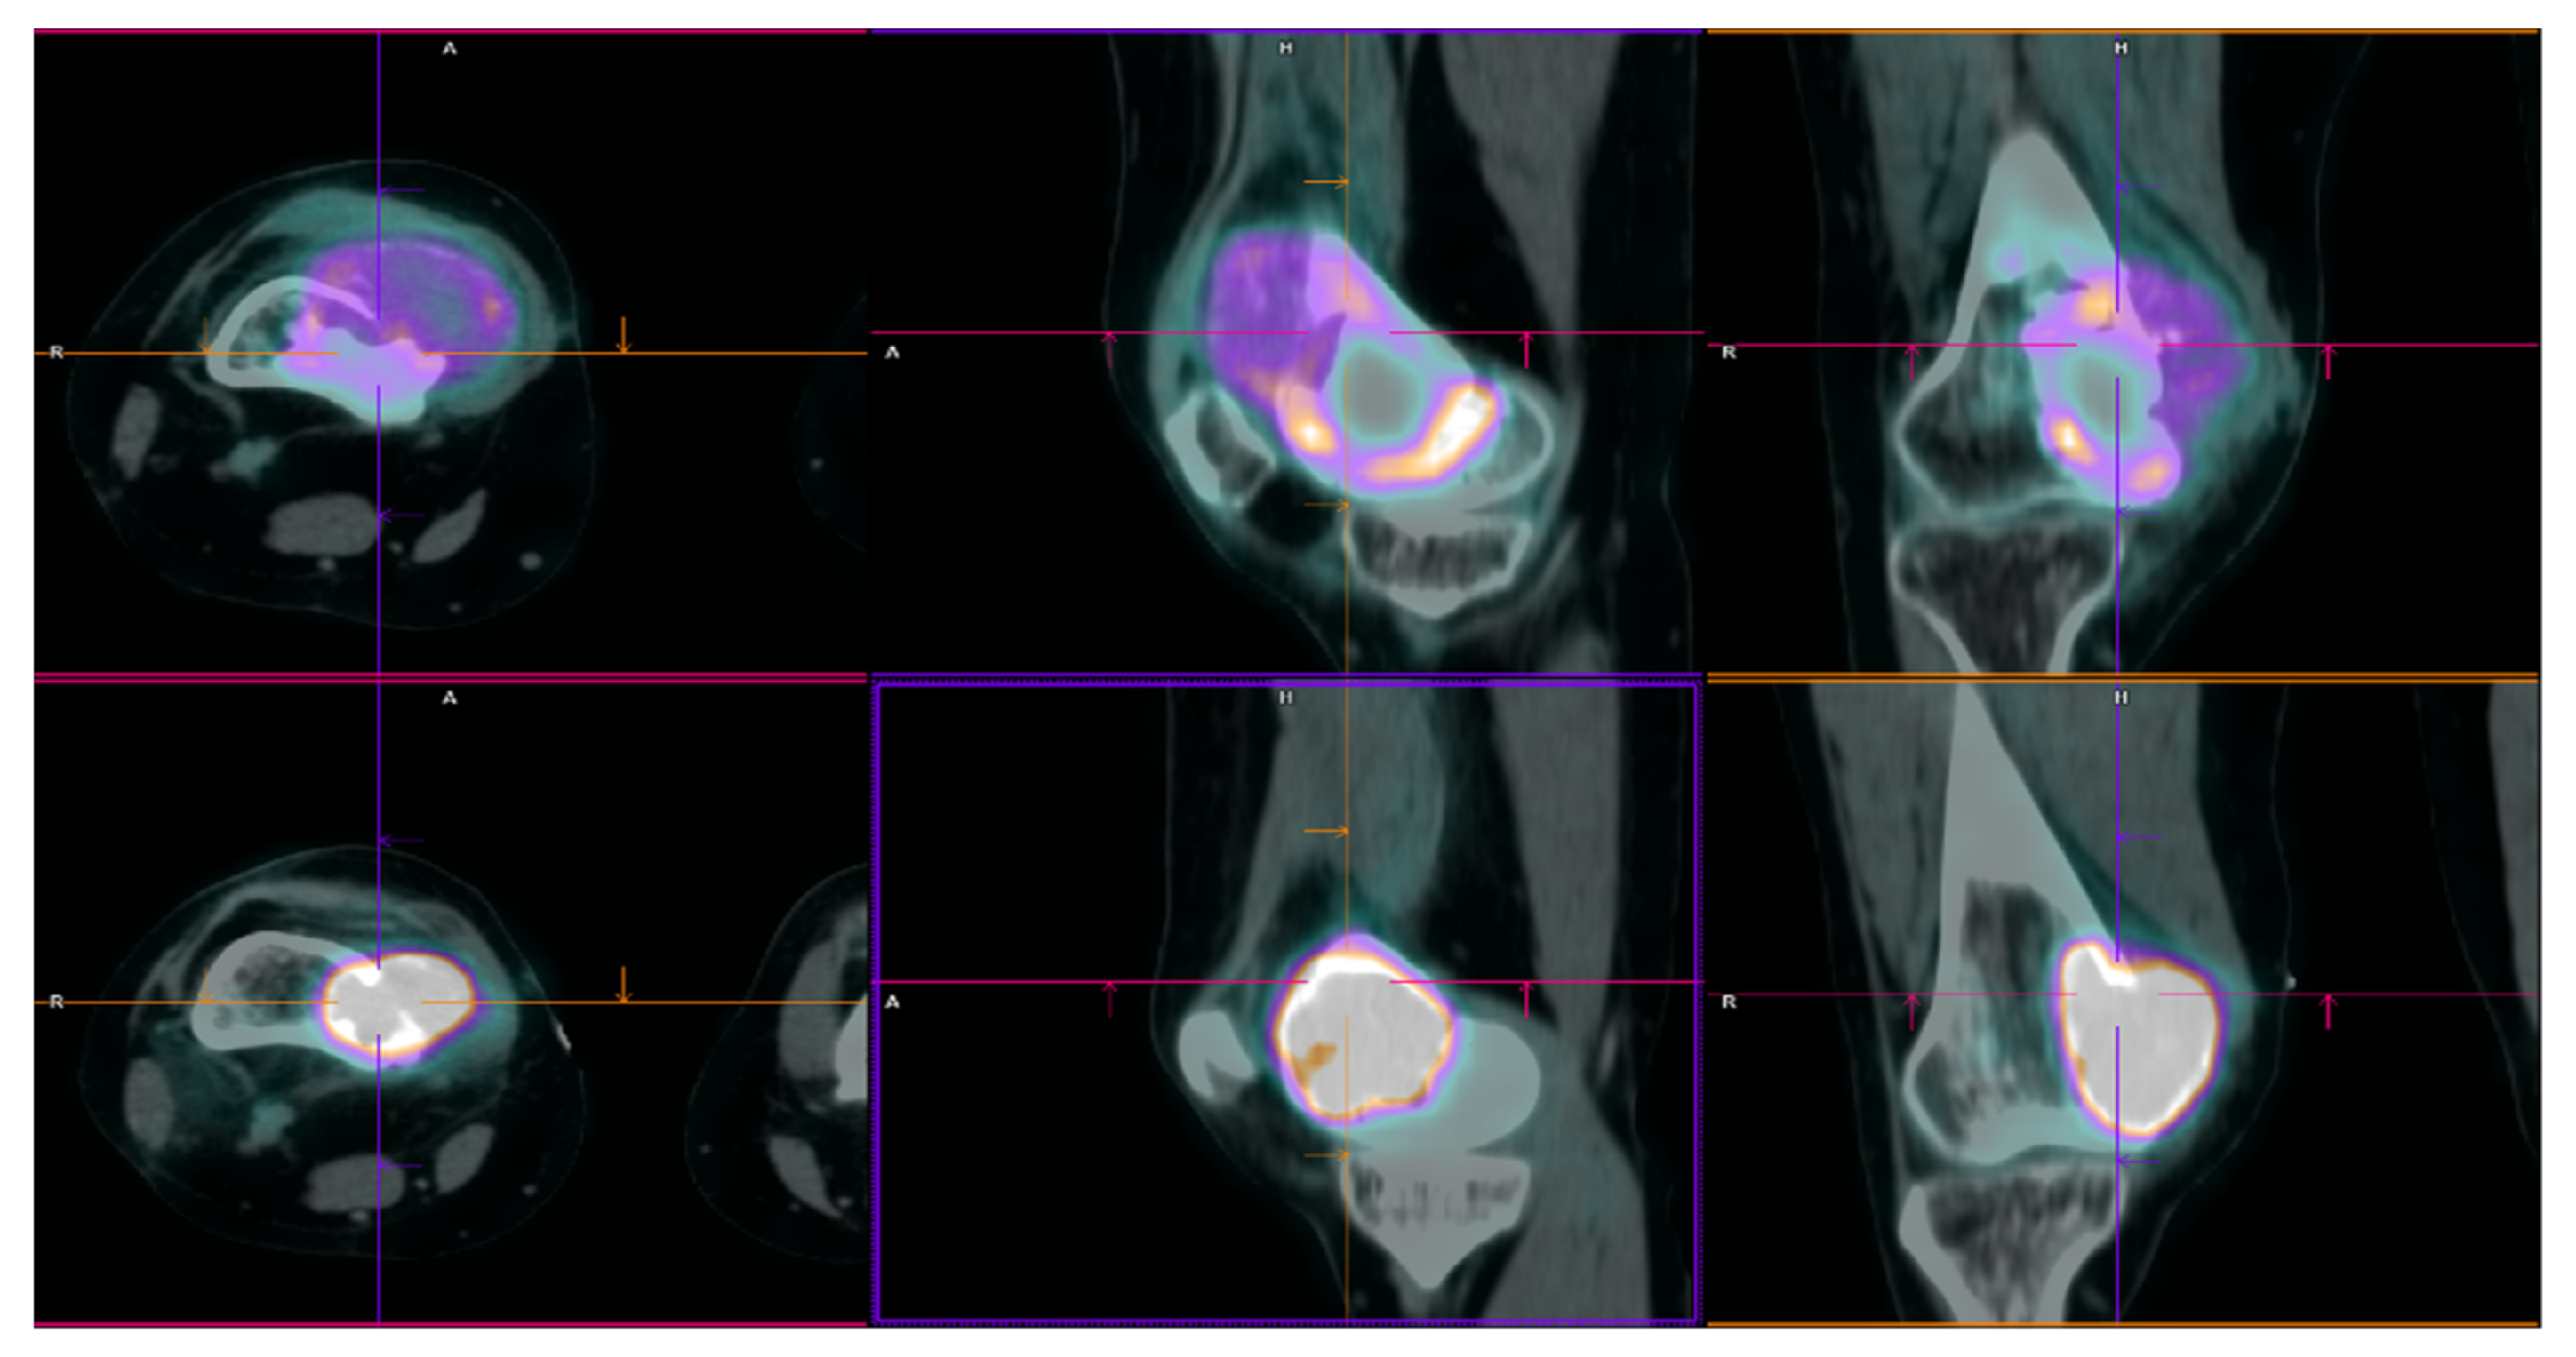

2.2. Patient 2

| Pt 2 | 48 | M | 0 | 16 November | Right tibia | Curettage and bone grafts | 20 October | Neoadj denosumab (6 cycles) | 21 February Extraarticular resection: malignant transformation of GCTB | EURO BOSS | NED | - | FU 21 December | 51 | 64 | 13 |